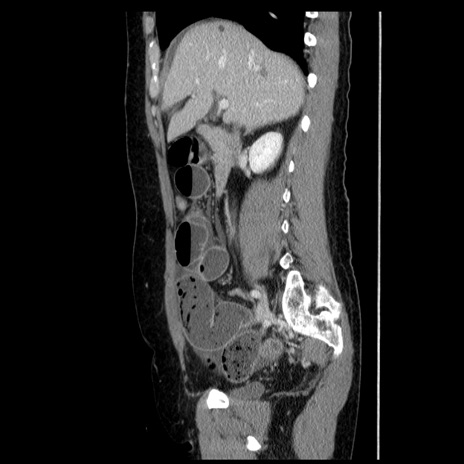

横断像

冠状断像

【症例】50歳代女性

【主訴】下腹部痛

【既往歴】卵巣癌術後(8年前に当院で卵巣摘出)